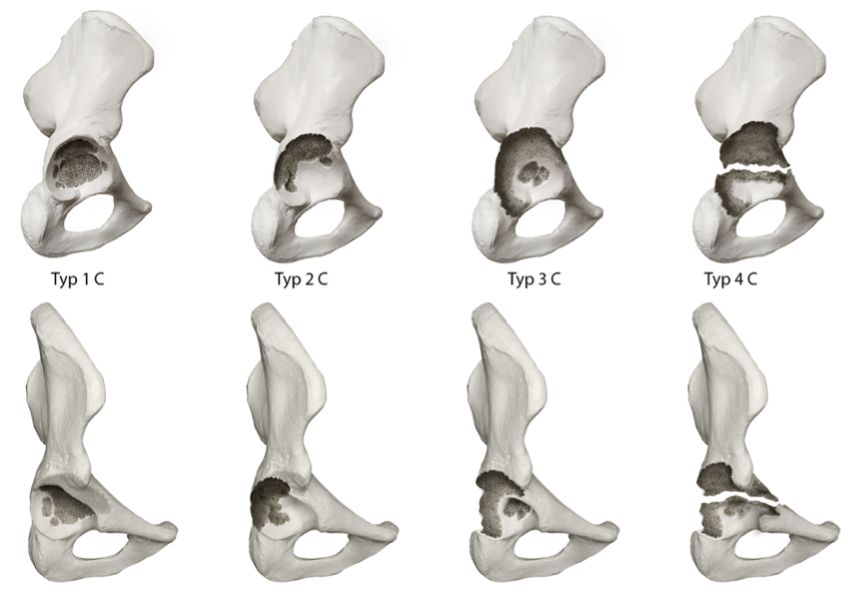

The ADC is based on the assessment of the integrity of the acetabular rim and load-bearing bony pelvic structures. It is classified into 4 main grades (1 to 4), that indicate the severity of the bony defect and 3 subclassifications each (A to C) defining the location of the lesion. The individual defect types are briefly summarized below. Figure 1 shows one example defect from each of the 4 main categories.

Type 1 defects:

These acetabular bone defects are characterized by an intact acetabular rim. Within subclassification A there are disseminated spongiosa bone defects, in subclassification B there is a superomedial defect shown and in subclassification C there is a medial acetabular fossa defect.

Type 2 defects:

In the group of type 2 defects the acetabular rim in the load-bearing zone is compromised up to a size of 10 mm. In this group, subclassification A defines a superolateral acetabular rim defect, subclassification B a dorsal acetabular rim defect and subclassification C the combination of A and B resulting in a superior and dorsal acetabular rim defect.

Type 3 defects:

The structure of the group of type 3 defects is identical to type 2 defects. However, in this type the size of the acetabular rim defect exceeds the 10 mm limit and is therefore called a structural defect.

Type 4 defects:

This type of defect covers the various versions of pelvic discontinuity Here the subclassification A−C refers to the extent of the bony defect of the superior acetabular fossa. Group A shows no relevant bone defect, Group B shows a superior acetabular rim defect of <10 mm and Group C a structural superior acetabular rim defect of >10 mm.